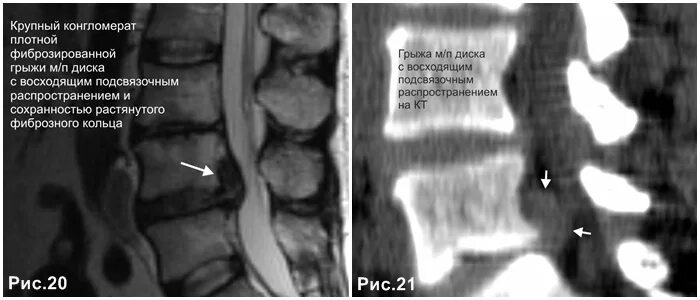

Каудальная миграция грыжи диска